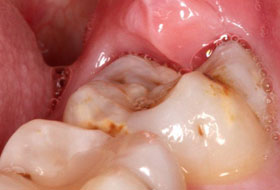

The gum overlying the tooth may get infected causing severe pain and discomfort radiating to the jaws, ear, temple region. The wisdom teeth, if they erupt in an abnormal position cause changes in the temporomandibular joint leading to problems over a period of time and also can damage to the adjacent teeth. The abnormal position of the teeth may cause difficulty in brushing and maintaining good hygiene of the teeth.